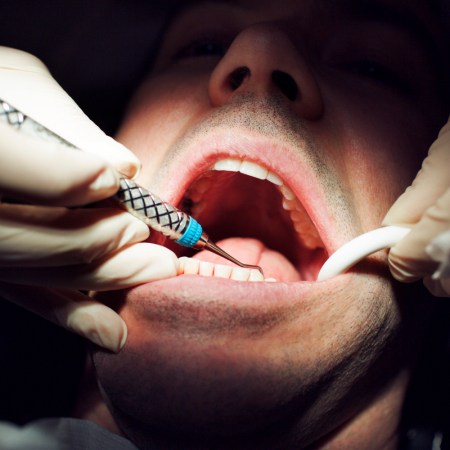

When you think about going to the dentist’s office, do you find yourself feeling a rush of fear, seemingly from nowhere? The good news — or the bad news — is that you’re far from alone in this. A recent WebMD article cites the statistic that between 9% and 20% of Americans view dental visits with apprehension. Here’s the thing, though — for as unnerving as modern dental technology can be, it used to be so much worse.